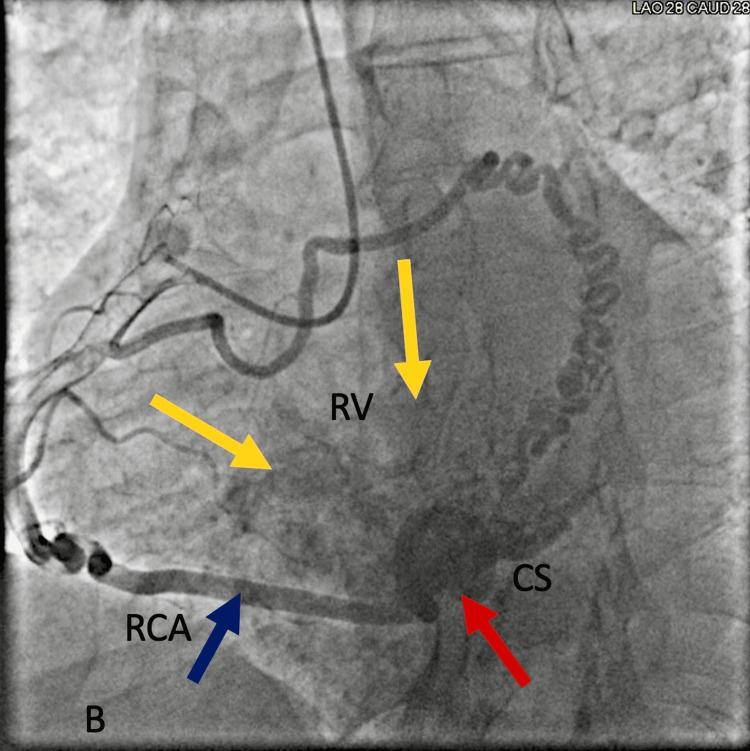

Coronary artery fistulas (CAFs) are rare vascular anomalies characterized by abnormal connections between coronary arteries and cardiac chambers or adjacent structures. Advances in cardiac interventions have led to an increasing recognition of acquired CAFs, which are typically congenital. We present a case of a 62-year-old male with a complex medical history, including hypertension, atrial fibrillation, and heart failure, who presented with exertional chest pain and palpitations. Diagnostic evaluation revealed a significant CAF originating from the right coronary artery (RCA) and terminating into the coronary sinus and right ventricle. Despite the absence of significant coronary artery occlusions, the fistula was deemed clinically significant due to its potential to cause myocardial ischemia. Management involved guideline-directed medical therapy and lifestyle modifications. This case underscores the importance of early recognition and appropriate management of CAFs to optimize patient outcomes. Further research is needed to better understand the natural history and optimal management strategies of CAFs.

冠状动脉瘘(CAFs)是一种罕见的血管异常,其特征是冠状动脉与心腔或相邻结构之间存在异常连接。心脏介入技术的进步使得人们越来越认识到获得性CAFs,而CAFs通常是先天性的。我们报告一例62岁男性病例,其有复杂的病史,包括高血压、心房颤动和心力衰竭,表现为劳力性胸痛和心悸。诊断评估发现一个源自右冠状动脉(RCA)并终止于冠状窦和右心室的大型冠状动脉瘘。尽管没有明显的冠状动脉闭塞,但由于该瘘管有导致心肌缺血的可能性,故被认为具有临床意义。治疗包括遵循指南的药物治疗和生活方式改变。该病例强调了早期识别和适当管理冠状动脉瘘以优化患者预后的重要性。需要进一步研究以更好地了解冠状动脉瘘的自然病程和最佳管理策略。